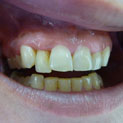

En estos casos han sido tratados con la filosofía de all-at-once, en la

misma sesión: